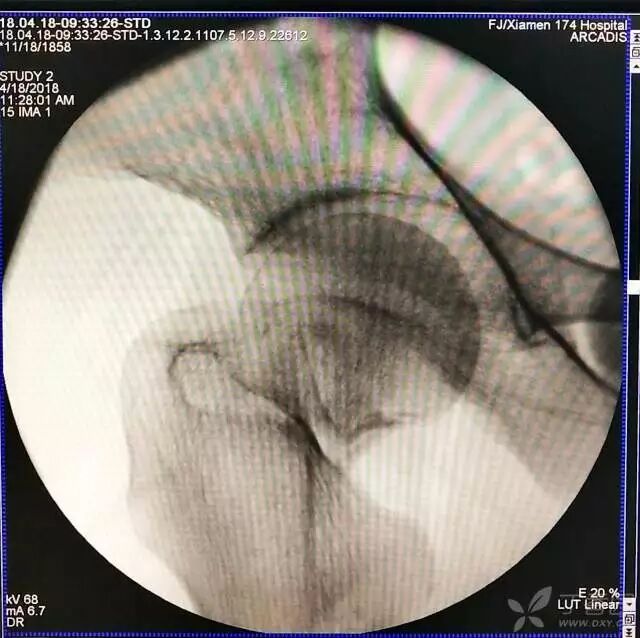

4. 先体外放置一枚导针导引进针方向

牵引床怎么用视频详解:如何不使用牵引床做好一台股骨颈骨折?_https://www.jmylbn.com_新闻资讯_第12张